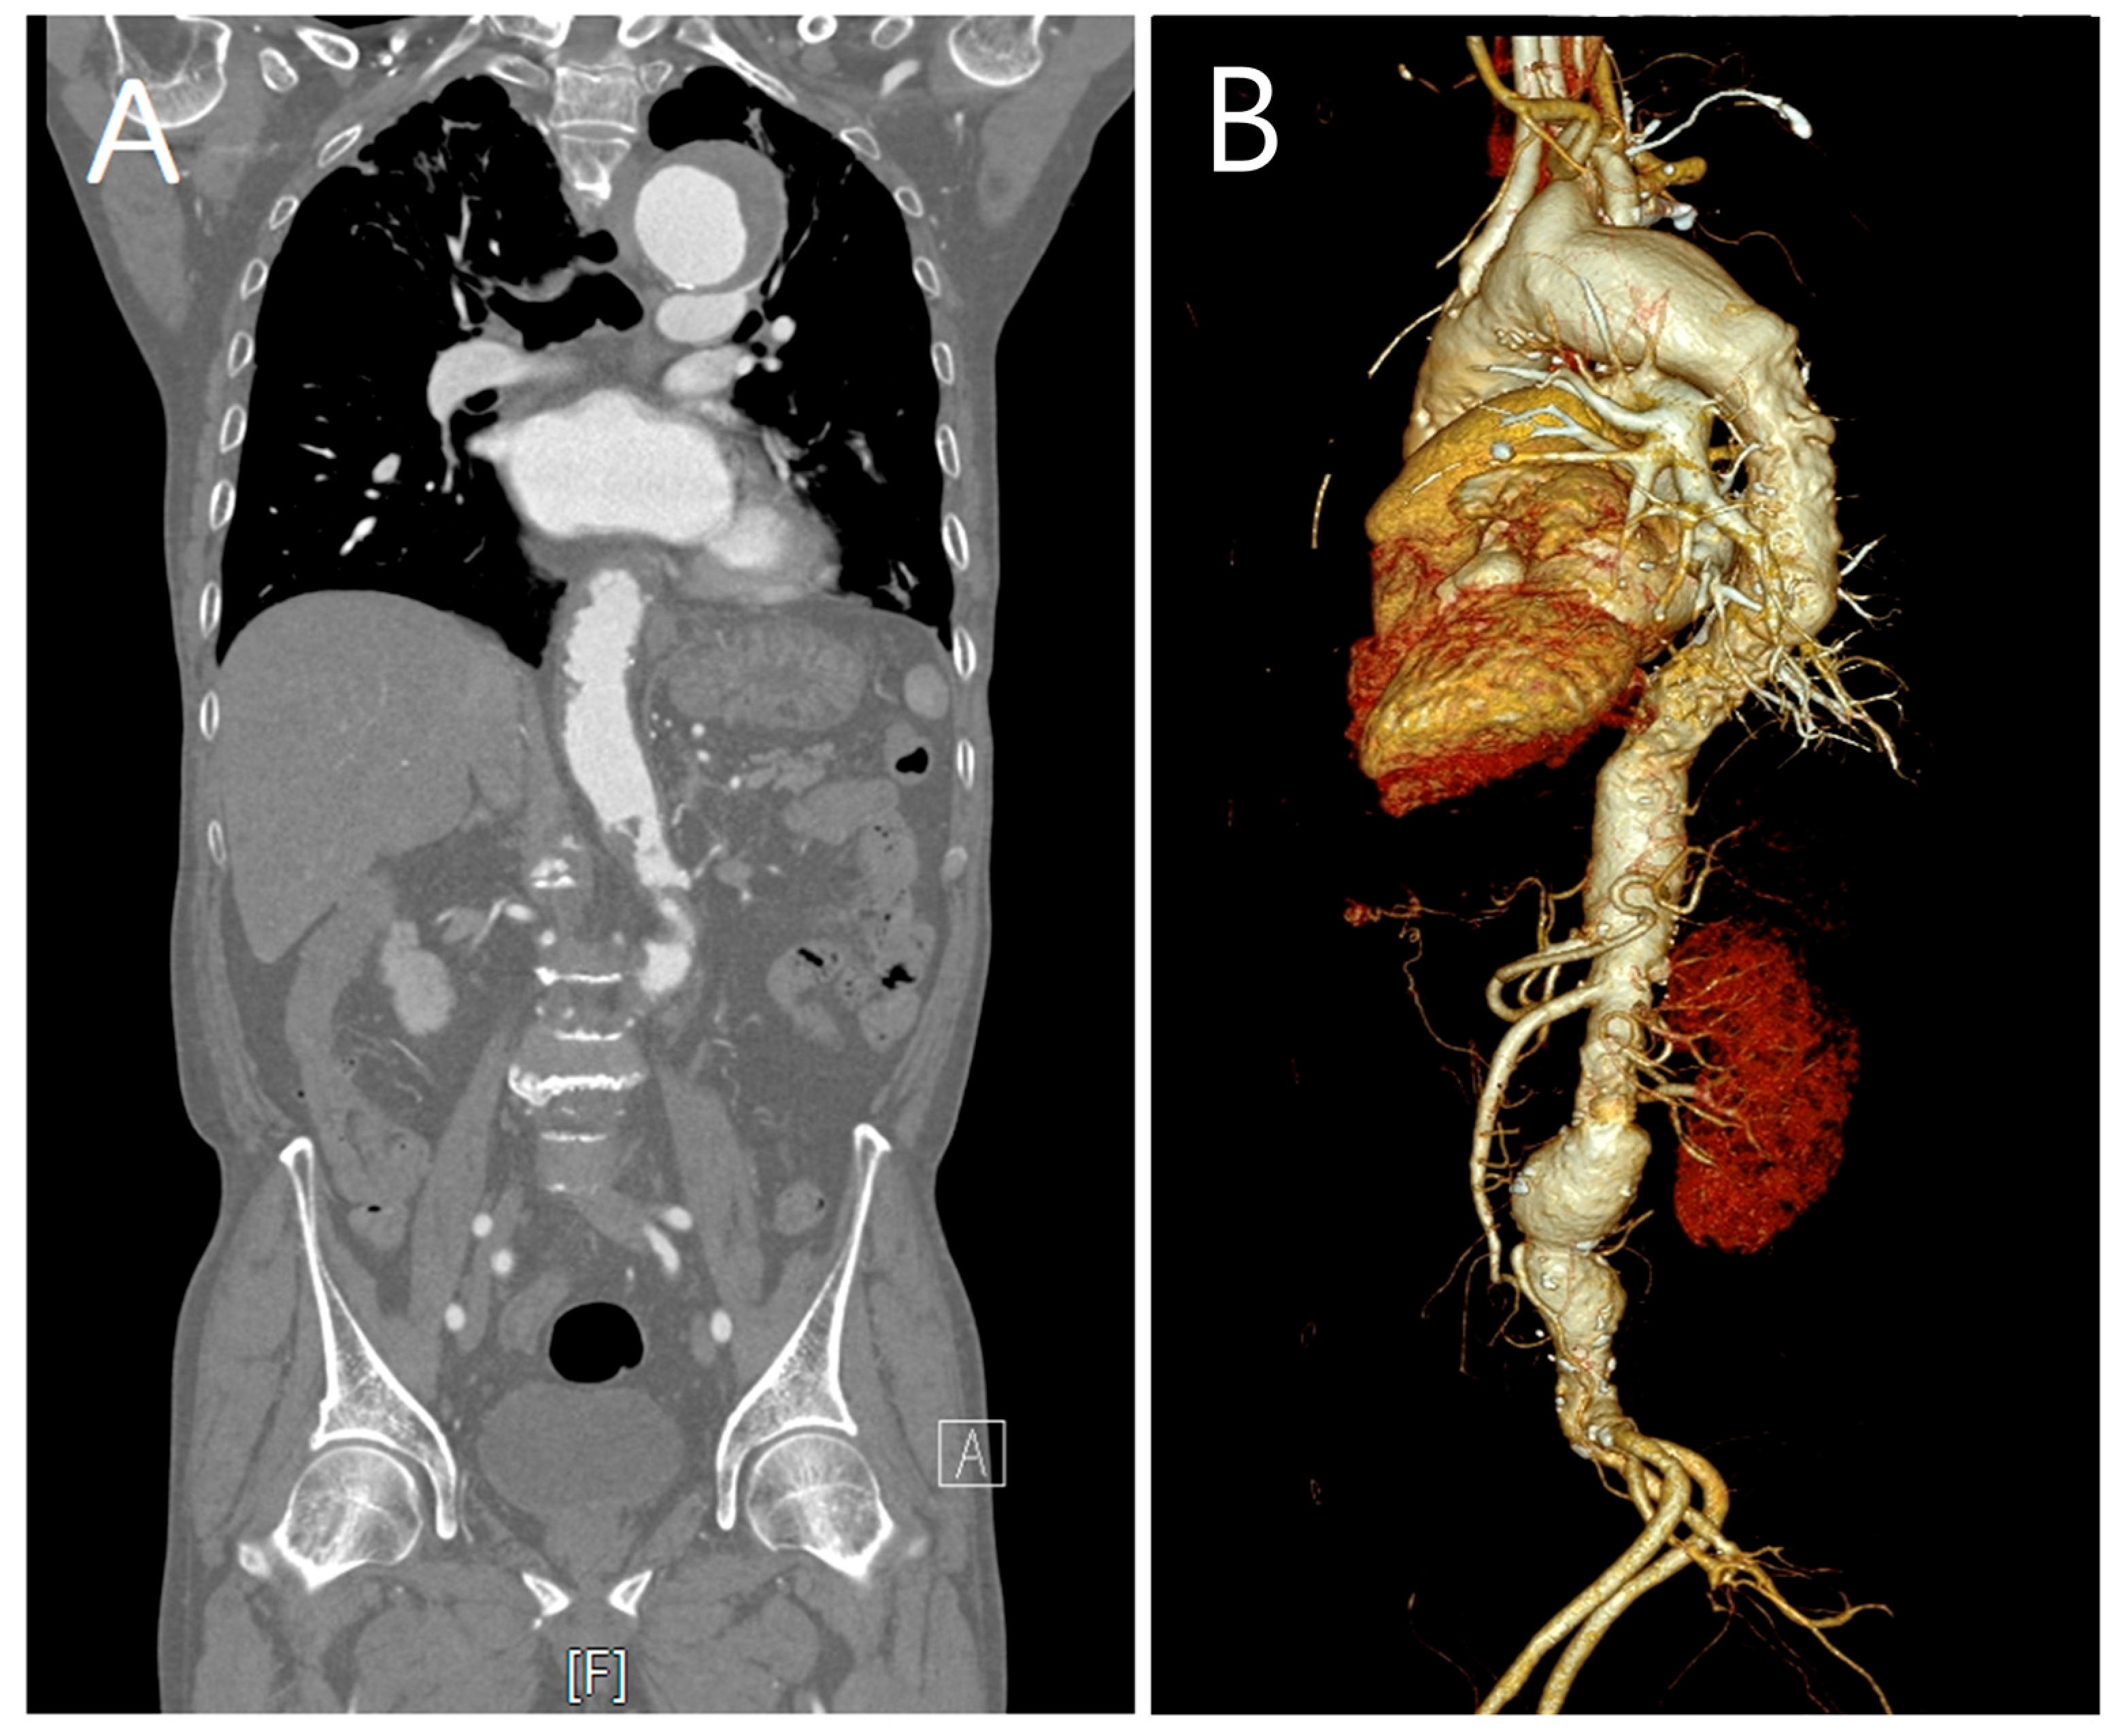

2. Case Description